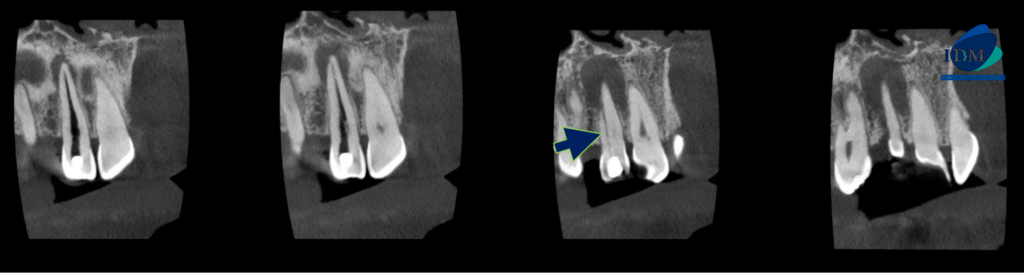

A la evaluación de la tomografía computarizada de campo reducido de la pieza 22 se observa (además de la restauración y la preparación endodontica parcial del conducto pulpar), una alteración de la morfología radicular caracterizada por la presencia de un surco palatino que va desde tercio cervical hasta el tercio apical y que ocasiona el ensanchamiento del espacio para el ligamento periodontal (vista en corte axial y transaxial), asimismo se observa la presencia de un proceso osteolítico periapical que ocasiona el adelgazamiento de las tablas óseas vestibular, palatina y del piso de fosa nasal de aparente origen endoperiodontal.

CORTES AXIALES